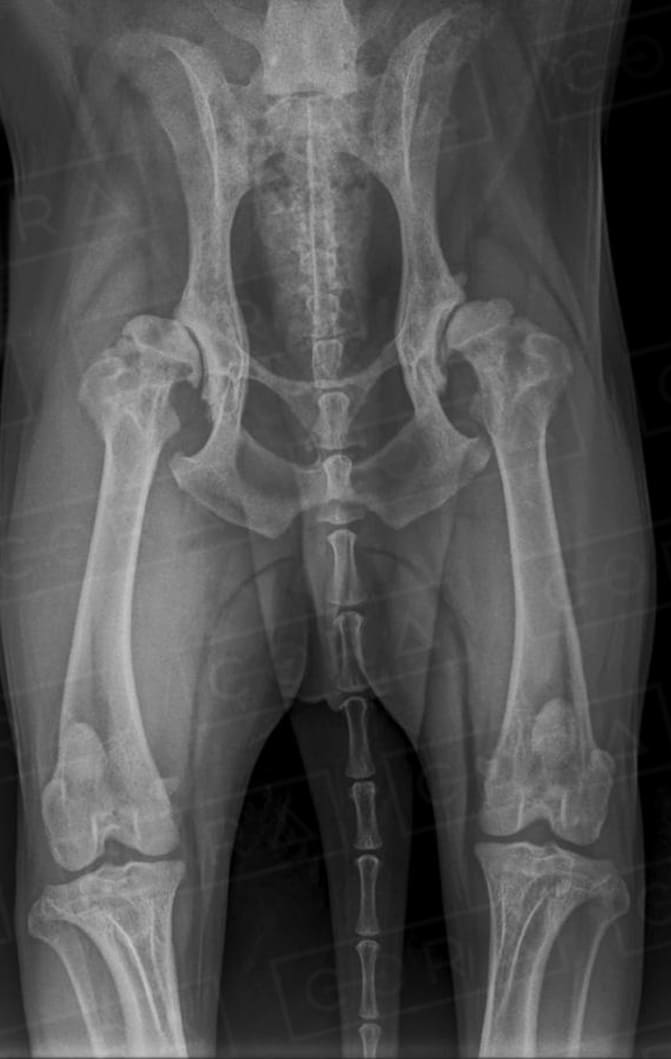

A sinais clínicos (DCF) é uma doença de característica genética e poligênica envolvendo uma ou ambas as articulações do quadril, causada pela instabilidade do quadril, levando a incongruência articular e desenvolvimento de osteoartose.

O diagnóstico é baseado na anamnese, exame físico e radiográfico simples. O diagnóstico precoce, em filhotes ainda assintomáticos, pode ser feito por meio do PennHIP, técnica de raio-x por distração articular, que estima o grau de instabilidade do quadril e risco de desenvolvimento de osteoartrose. O diagnóstico precoce possibilita um melhor prognóstico e mais qualidade de vida ao animal.